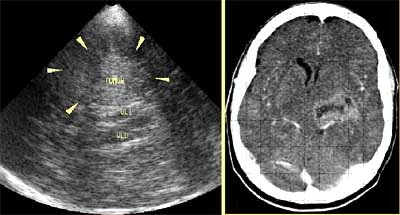

![]() |

| Aneurisma de la arteria basal en un hombre de 48 años. Imagen cortesía del Dr. Orlando Valls Pérez. |

| Teratoma cerebral en un paciente de sexo masculino de 56 años de edad (izquierda) con correlación tomográfica (derecha) Imagen cortesía del Dr. Orlando Valls Pérez. |

Los tumores cerebrales se pueden identificar como masas ecogénicas rodeadas por un halo hipoecoico. Las masas heterogéneas pueden ser consecuencia de necrosis, quistes o calcificaciones.